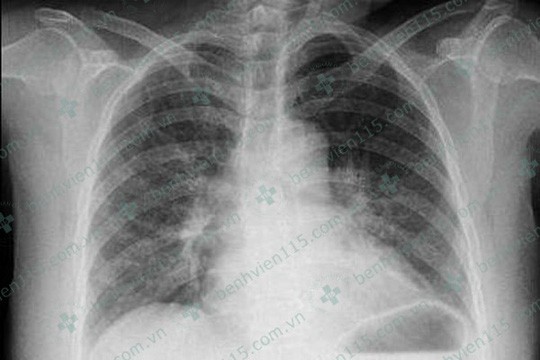

Kiểm tra X-quang phổi bệnh nhân không ghi nhận gì bất thường

Ngày 24/3, Bệnh viện Nhân dân 115 TP HCM cho biêt bệnh viên đang tiếp nhận một trường hợp bị biến chứng cấp tính hiếm gặp do bị ong đốt. Bệnh nhân là bà N.T.T.B (61 tuổi, ngụ tỉnh Bình Thuận), nhập viện trong tình trạng đau ngực dữ dội, khó thở, suy tim cấp.

Bệnh nhân được cấp cứu tại một bệnh viện địa phương với chẩn đoán hội chứng mạch vành cấp, sau đó chuyển đến Bệnh viện Nhân dân 115. Tại bệnh viện, các bác sĩ Khoa Tim mạch Tổng quát xác định bệnh nhân bị nhồi máu cơ tim cấp chênh lên vùng trước rộng giờ 22. Bệnh nhân được điều trị tích cực, sau vài ngày đã giảm khó thở, bớt đau ngực, sinh hiệu ổn định, tim đều…

Theo BS Châu Minh Thông, Khoa Tim mạch Tổng quát Bệnh viện Nhân dân 115 (người trực tiếp điều trị cho bệnh nhân) bị nhồi máu cơ tim sau khi bị ong đốt là một biến chứng hiếm gặp, cấp tính, tỉ lệ tử vong cao, diễn tiến phức tạp. "Vì vậy, đối với các trường hợp sau khi bị ong đốt, triệu chứng đau ngực ở bệnh nhân cần được xem xét cẩn thận, thực hiện các phương pháp cận lâm sàng cần thiết để loại trừ nhồi máu cơ tim", BS Thông lưu ý.